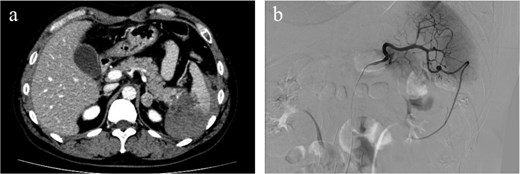

A 47-year-old male presented to our emergency department with sudden onset of left upper-quadrant (LUQ) abdominal pain that began 3 days earlier and an episode of dizziness that had happened on the day of presentation. His medical history included gout and benign prostatic hyperplasia, for which he was regularly prescribed febuxostat. There was no history of anticoagulant use. He denied any history of alcohol or illegal drug use. There was no history of taking nutritional supplements prior to his initial visit. There was no family history of similar events or hematological disorders. The patient had no history of recent trauma or involvement in contact sports. He was engaged in the ferry business and worked as a ferryman. On arrival, his vital signs were stable with a blood pressure of 135/88 mmHg, heart rate of 97 bpm, body temperature of 35.6°C, and oxygen saturation of 100% on room air. Physical examination revealed mild tenderness in the LUQ without rebound tenderness. Laboratory examination showed leukocytosis with a white blood cell count of 16 600/μl and an elevated C-reactive protein level of 4.11 mg/dl. The hemoglobin level was 15.5 g/dl, showing no decrease. Both prothrombin time and activated partial thromboplastin time were within normal limits (prothrombin time-international normalized ratio: 0.89, activated partial thromboplastin time: 35.2 s). Platelet count was also within the normal range (231 000/μl). There were no increases in amylase or lipase level (amylase: 44 U/l, lipase: 8 U/l). Contrast-enhanced computed tomography (CT) revealed hemorrhagic ascites predominantly surrounding the spleen, suggestive of splenic rupture, although no active bleeding or splenic masses were observed (Fig. 1a). The size of the spleen was within normal limits (92 × 49 mm). There were no available previous images because this was the initial visit of the patient. CT revealed advanced hepatosteatosis, but no other morphological abnormalities suggestive of liver disease were observed. A follow-up CT scan 5 h after the initial scan showed only a slight increase in hemorrhagic ascites with no signs of active hemorrhage. Angiography performed the same day showed no active bleeding or aneurysm formation in the splenic artery (Fig. 1b). Given that the patient remained hemodynamically stable and no decline in hemoglobin level was observed, non-operative management was initially selected. Magnetic resonance imaging and endoscopic ultrasonography were performed to identify the cause of the splenic rupture; however, they failed to detect any underlying conditions. Although we could not determine the cause of the rupture, the patient was stable after admission and was discharged on the seventh hospital day. Given the persistent risk, laparoscopic splenectomy was performed 24 days after the initial presentation. A large hematoma is observed around the spleen (Fig. 2). Owing to the hemorrhagic event, dense adhesions were formed between the spleen and surrounding tissues, particularly the diaphragm. The adhesion between the pancreatic tail and spleen was strong, making it challenging to separate them. The pancreatic tail was resected along the spleen. Other than biochemical pancreatic leak, no post-operative events occurred, and the patient was discharged on post-operative Day 12. The resected spleen was histologically normal and no causal lesions were noted. A hematology consultation was obtained to evaluate the possibility of an underlying hematologic disorder; however, lymphoma, leukemia, myeloproliferative neoplasms, and other hematologic disorders that could potentially cause splenic rupture were ruled out based on laboratory findings, imaging studies, and histopathological examination. We discussed the patient’s condition with the department of pathology, and concluded that spontaneous rupture of a normal spleen was the most likely diagnosis.

Hemorrhagic ascites were observed primarily around the spleen, suggesting splenic rupture. No contrast extravasation was observed and active bleeding was not suspected (a). Angiography showed no active bleeding or splenic artery aneurysms were observed on angiography (b).